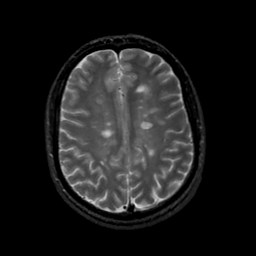

MR Study #18, July 21, 1991 -- Slice #34

[Home][Help][Clinical][Tour 1][Tour 2] Slice 34